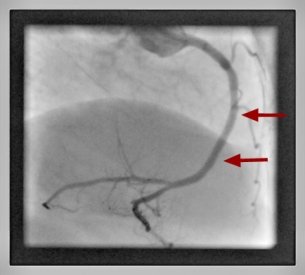

Percutane Koronarintervention Herzkranzgefäßeinengung behandelt Kardiologie Garbsen

Herzkranzgefäß nach Intervention

Im Anschluss wird in der Regel zur Stabilisierung des Ergebnisses und zur Verhinderung einer Wiedereinengung (Re-Stenose) eine Gefäßstütze (Stent) eingesetzt. Während der Ausdehnungsbehandlung kann ein kurzzeitiges Druckgefühl im Brustkorb auftreten.